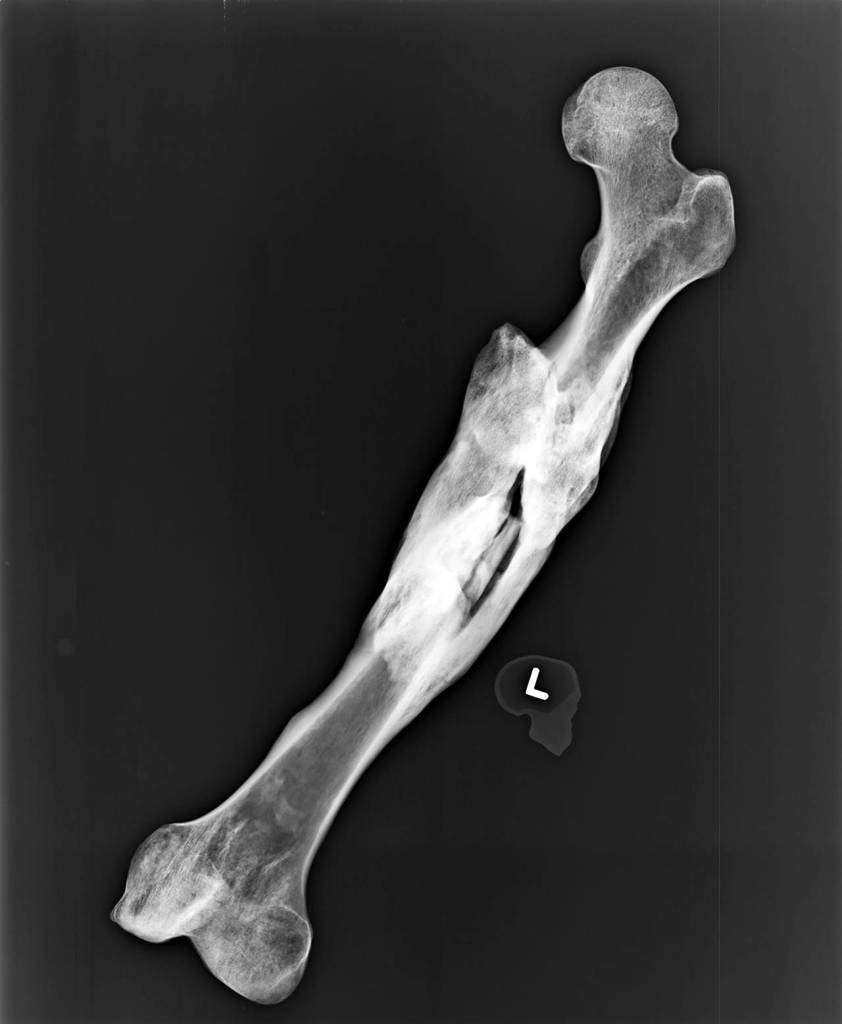

Picture a bone, the kind caricatured on a dog treat: smooth, straight and normal, with two knobs on each end. That’s a rough idea of the man’s right femur, the biggest and strongest bone in the body.

On his left side, he’d been living with a shattered thigh.

The X-ray shows the middle third of the bone stuck out like the claw of an ice scraper. We know he lived with it broken like that, because it healed, in a horrific way.

He would’ve stood two inches shorter on his left leg.

The break has telltale signs of a fracture that was never reset, according to the Snohomish County Medical Examiner’s Office. It grew worse over time.

Detectives believe he shuffled around on the injury for years, perhaps. There’s little doubt that he lived with chronic pain.

“We’ve never seen a fracture that healed like that,” Scharf said. “It’s almost like he was in a Third World country, or he just avoided medical help altogether.”